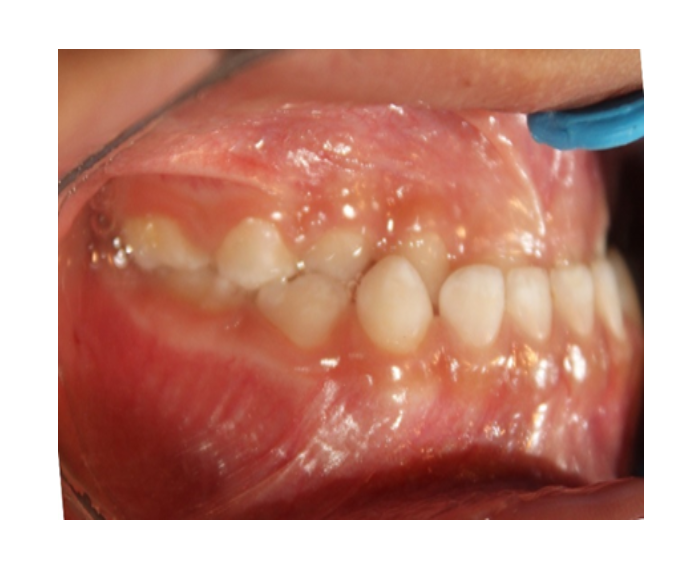

Mordida Cruzada posterior unilateral